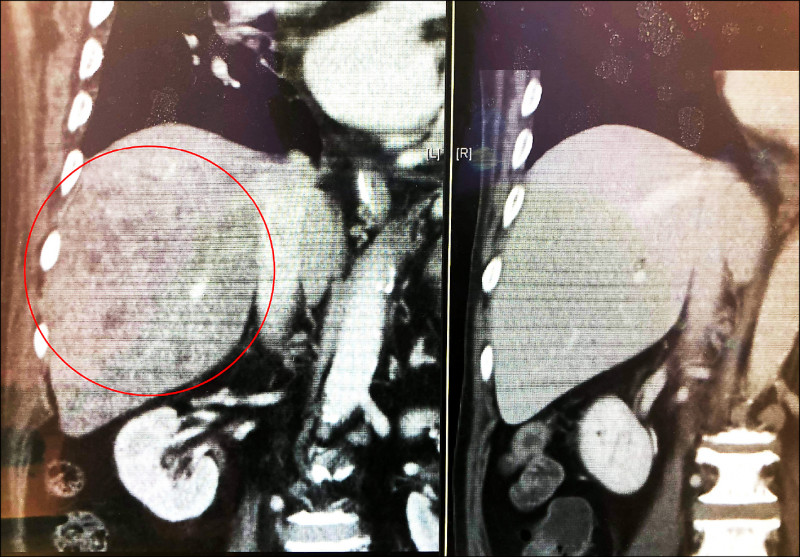

台中醫院神經內科醫師王星翰表示,大多數人都以為失智症是很正常,但是老翁退化速度太快了,讓他覺得不太合理,且發現范翁的腦脊髓液有發炎,而且體力非常差,幾乎全天臥床,甚至還出現水腫現象,因此再度安排檢查,發現肝臟竟有腫瘤,化驗後確認為肝臟淋巴癌。